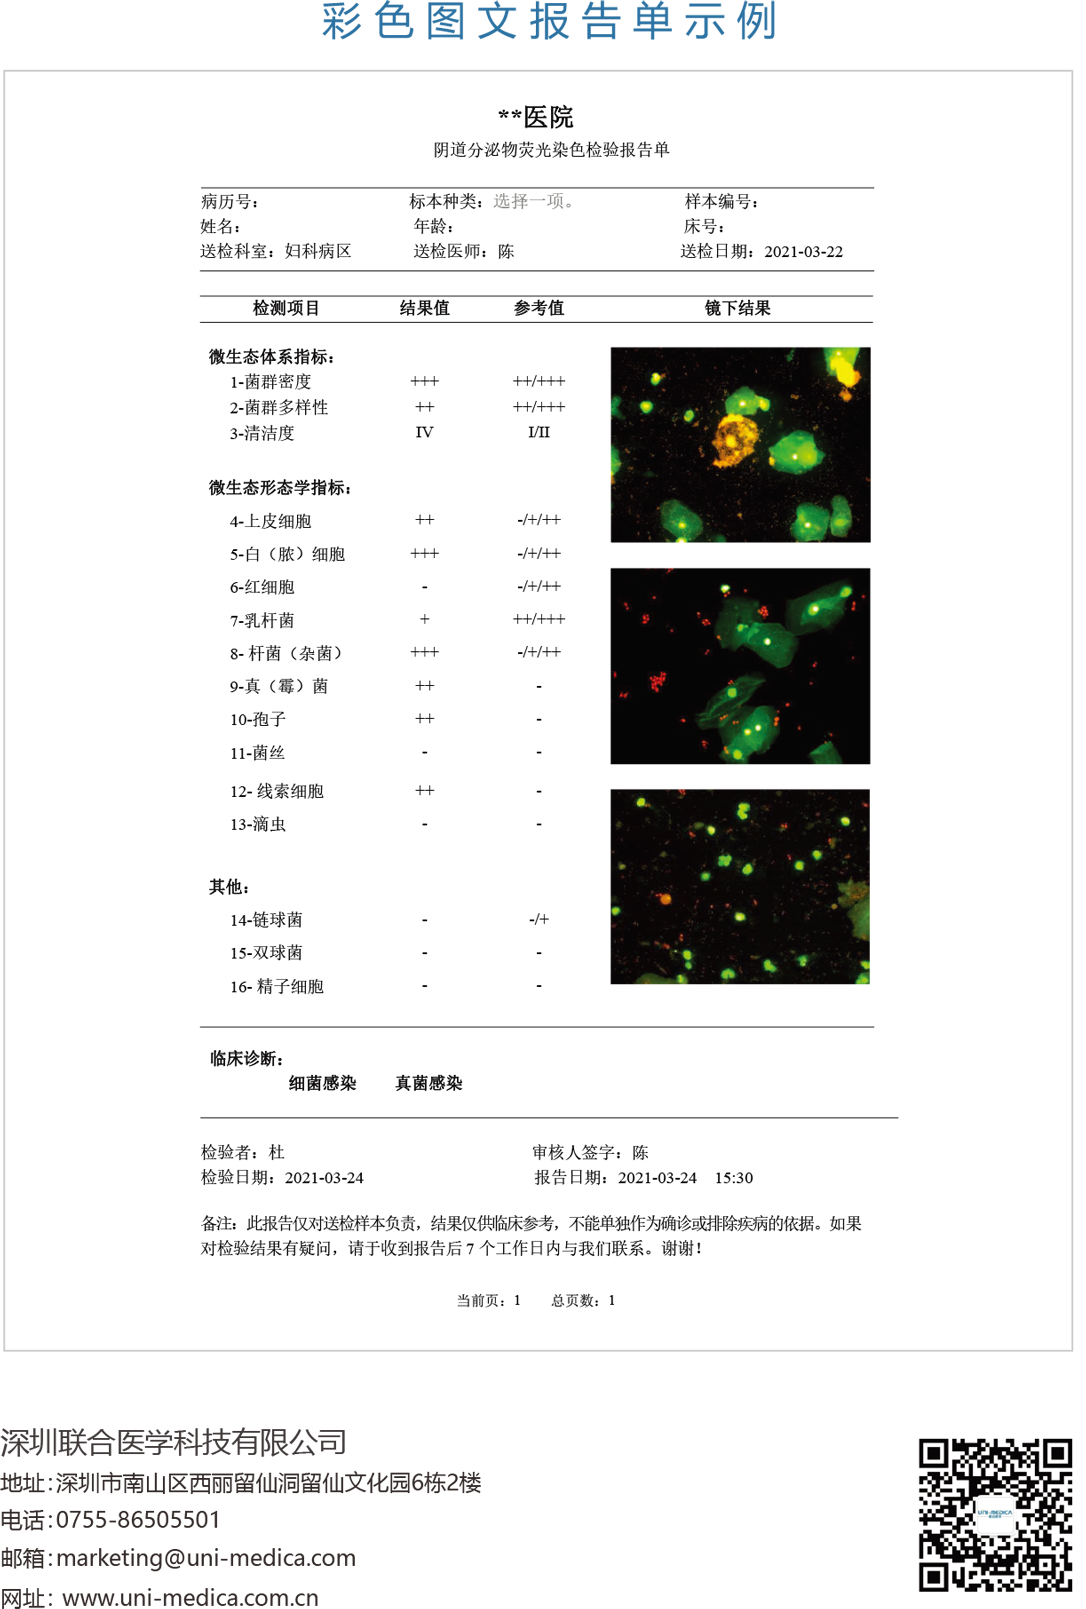

免疫荧光法结果展示及判读示例

阴道分泌物多重免疫荧光染色技术,具备形态学与荧光学的双重优势。可以同时对上皮细胞,白细胞,乳酸杆菌,线索细胞,念珠菌和毛滴虫等进行染色区分,既能检测阴道相关病原体感染,也能评估其阴道微生态和阴道清洁度等是否正常,为临床的快速诊断和治疗提供帮助。

上皮细胞/白细胞

绿色荧光

上皮细胞:作为内质控

白细胞:判定炎症程度

(清洁度)

线索细胞

橙黄色荧光

边缘不规则,模糊大小

与上皮细胞一致

念球菌

橙红色荧光

孢子形态直径3-6 μm

明显大于细菌,小于滴虫

毛滴虫

梨形或椭圆形,直径

10~13 μm稍大于白细胞